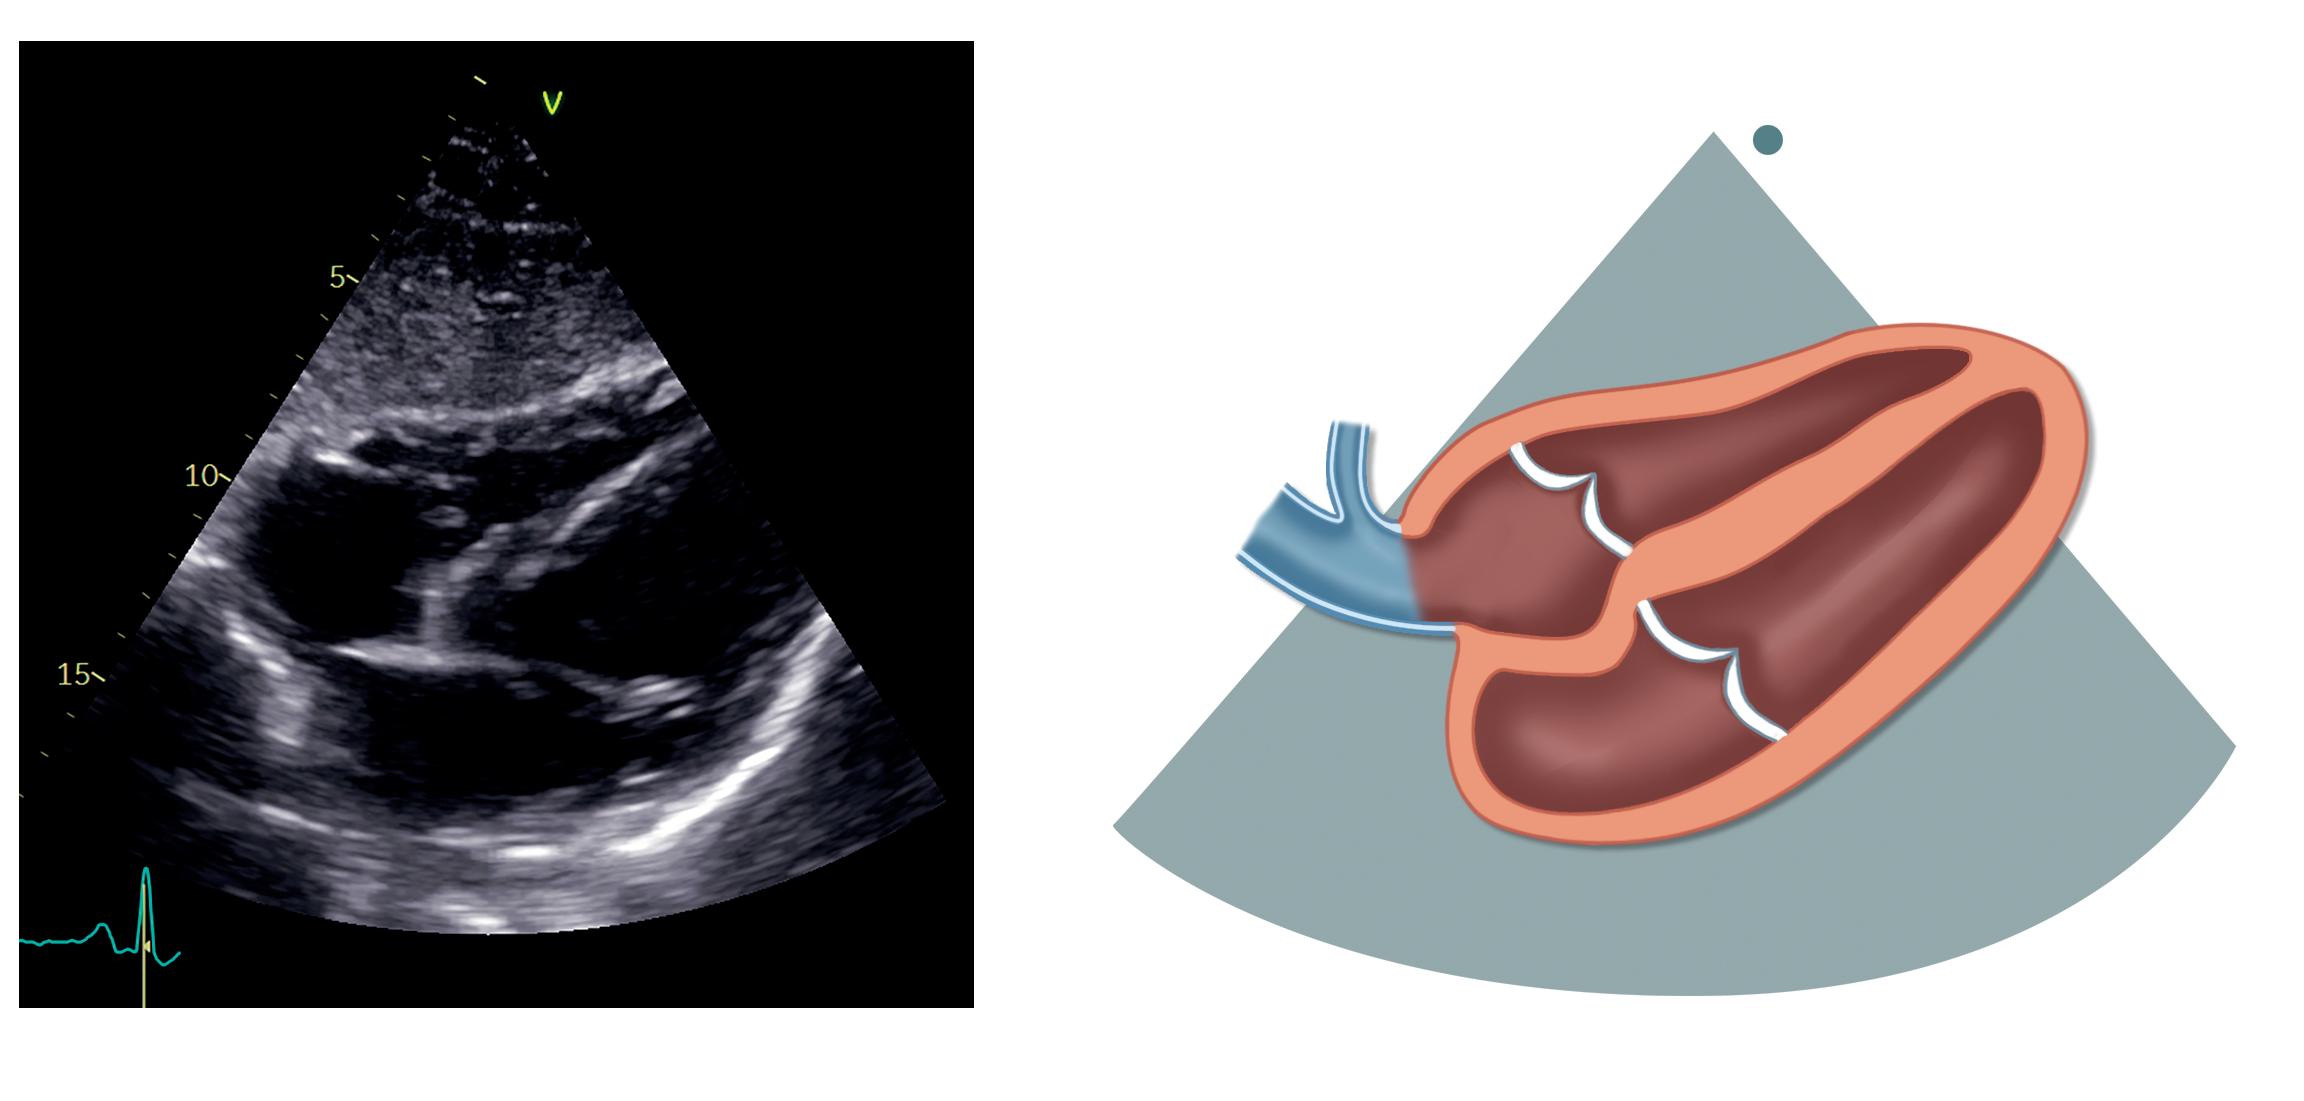

Apikal 2-kammerprojeksjon

Med utgangspunkt i apikal 4-kammerprojeksjon roteres transduseren 60–90 grader mot klokken slik at markøren peker omtrent mot venstre skulder og høyre ventrikkel ikke lenger er synlig til venstre i bildet (figur 2.8).

Øverst i bildet ses venstre ventrikkel med inferiore vegg til venstre og anteriore vegg til høyre, og nederst i bildet ligger venstre atrium. Mitralklaffen er plassert mellom dem, og litt avhengig av rotasjonen

Venstre ventrikkel (VV)

Mitralkla en (MK)

Venstre atrium (VA)

på transduseren kan man fremstille begge papillemusklene med den anterolaterale til høyre og den posteromediale til venstre. Klaffen kan fremstilles som et «interkommissuralbilde» med P1-segmentet til høyre, A2-segmentet i midten og P3-segmentet til venstre (mer om mitralklaffens segmenter i kapittel 7).

Sinus coronarius kan noen ganger ses som tverrsnittet av et kar ved atrioventrikulærfuren til venstre i bildet. Deler av venstre aurikkel kan ses til høyre i bildet som en utposning på venstre atrium rett under mitralplanet. Øvre venstre lungevene kan noen ganger ses munne ut i venstre atrium under aurikkelen til høyre i bildet.

Tabell 2.8 lister opp sentrale målinger i apikal 2-kammerprojeksjon.

Tabell 2.8: Sentrale målinger i apikal 2-kammerprojeksjon

Målinger i apikal 2-kammerprojeksjon

Venstre ventrikkels volum og EF (Simpsons metode)

Venstre atriums volum (Simpsons metode, endesystolisk)

Apikal langakseprojeksjon (apikal 3-kammerprojeksjon)

Fra apikal 2-kammerprojeksjon roteres transduseren ytterligere 60 grader mot klokken slik at markøren pe-

28 K APITTEL 2

VV VA

MK

Figur 2.8: Apikal 2-kammerprojeksjon

ker mot pasientens høyre skulder og man ser venstre ventrikkel, venstre atrium, LVOT og aortaklaff, samt en liten flik av høyre ventrikkel til høyre i bildet (figur

2.9). Denne projeksjonen viser i hovedsak det samme som parasternal langakse, bortsett fra at apex også fremstilles.